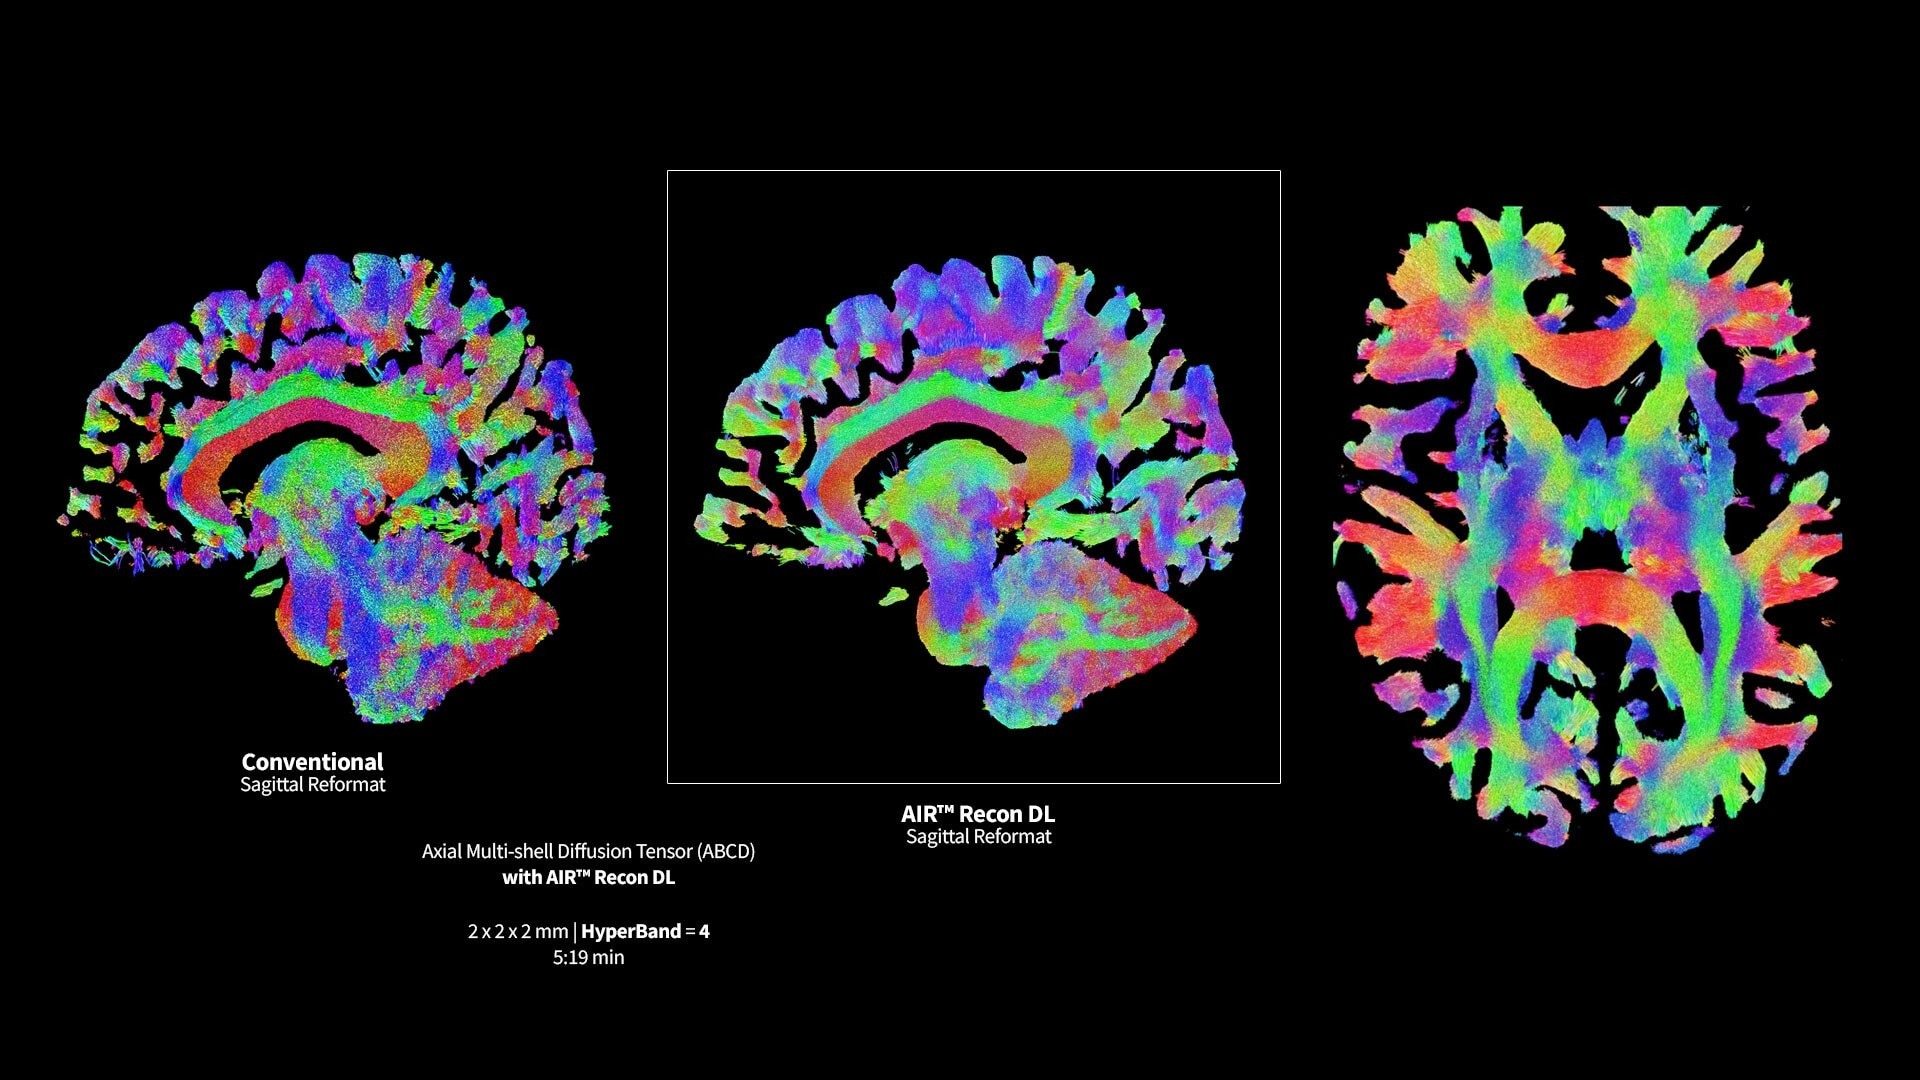

<p>AIR Recon DL</p>

Learn more ico-caret-right

<p>Advanced DWI</p>

Read case study ico-caret-right

MR image reconstruction with AIR Recon DL

Evolve your MRI scanner's capabilities: experience exceptional image quality without compromising scan time.